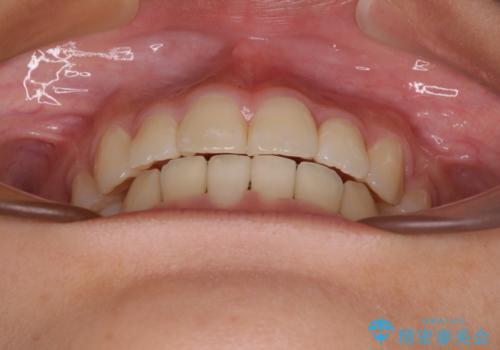

急速拡大後、歯列はきれいに並んだのですが、口元が出っ歯になってしまったため、速やかに抜歯を行い、治療期間がいたずらに遅延することのないようにしました。